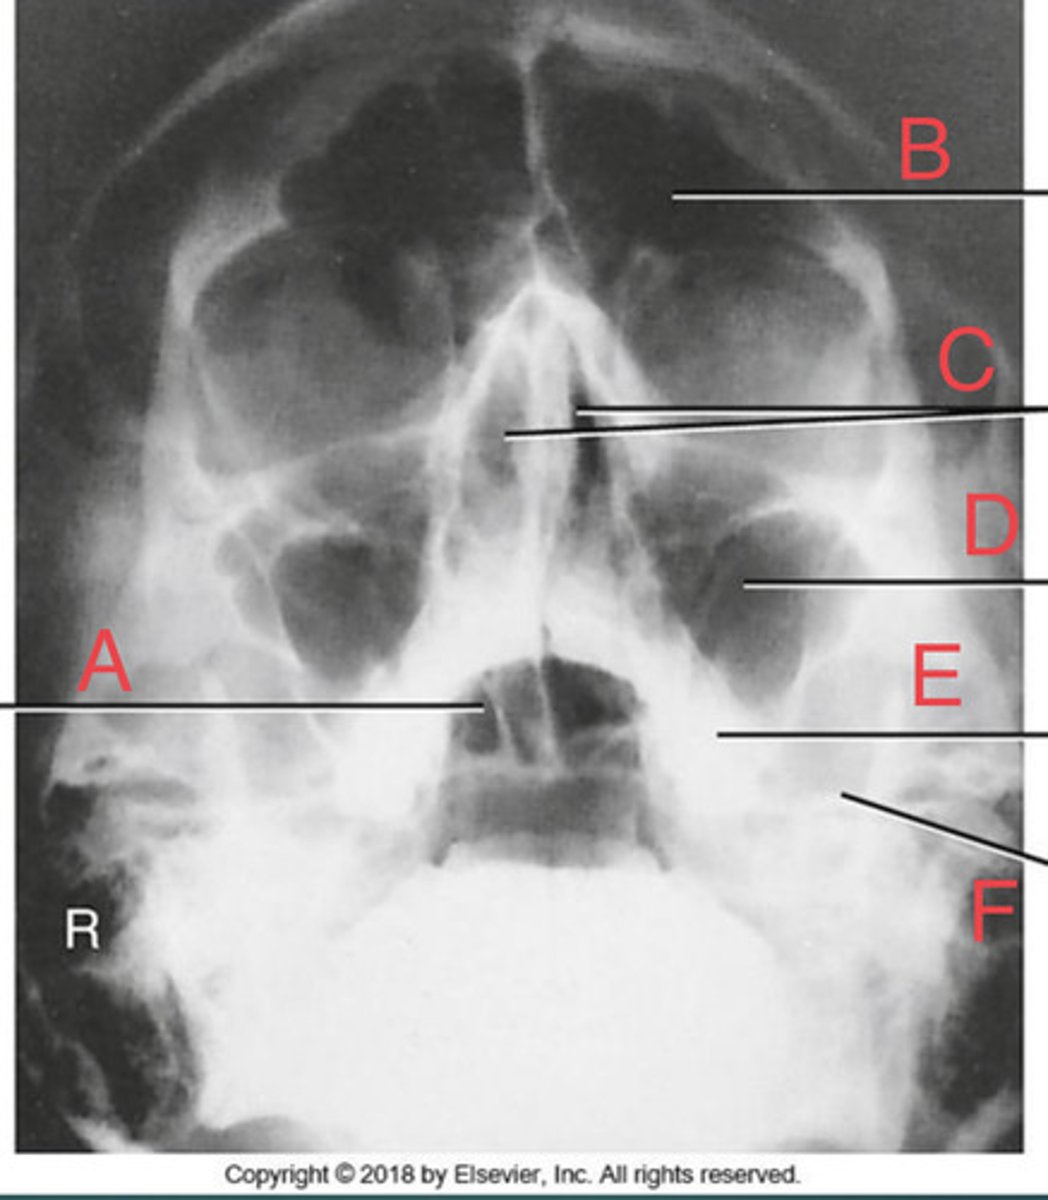

Waters sinus method

What projection?

r. frontal sinus of the frontal bone

A.

R. Maxillary sinus of maxilla

B.

R. petrous ridge of temporal bone

C.

bony nasal septum

D.

L. inferior orbital fissure of sphenoid bone

E.

Sphenoid sinus of sphenoid bone

F.

bony nasal septum

E.